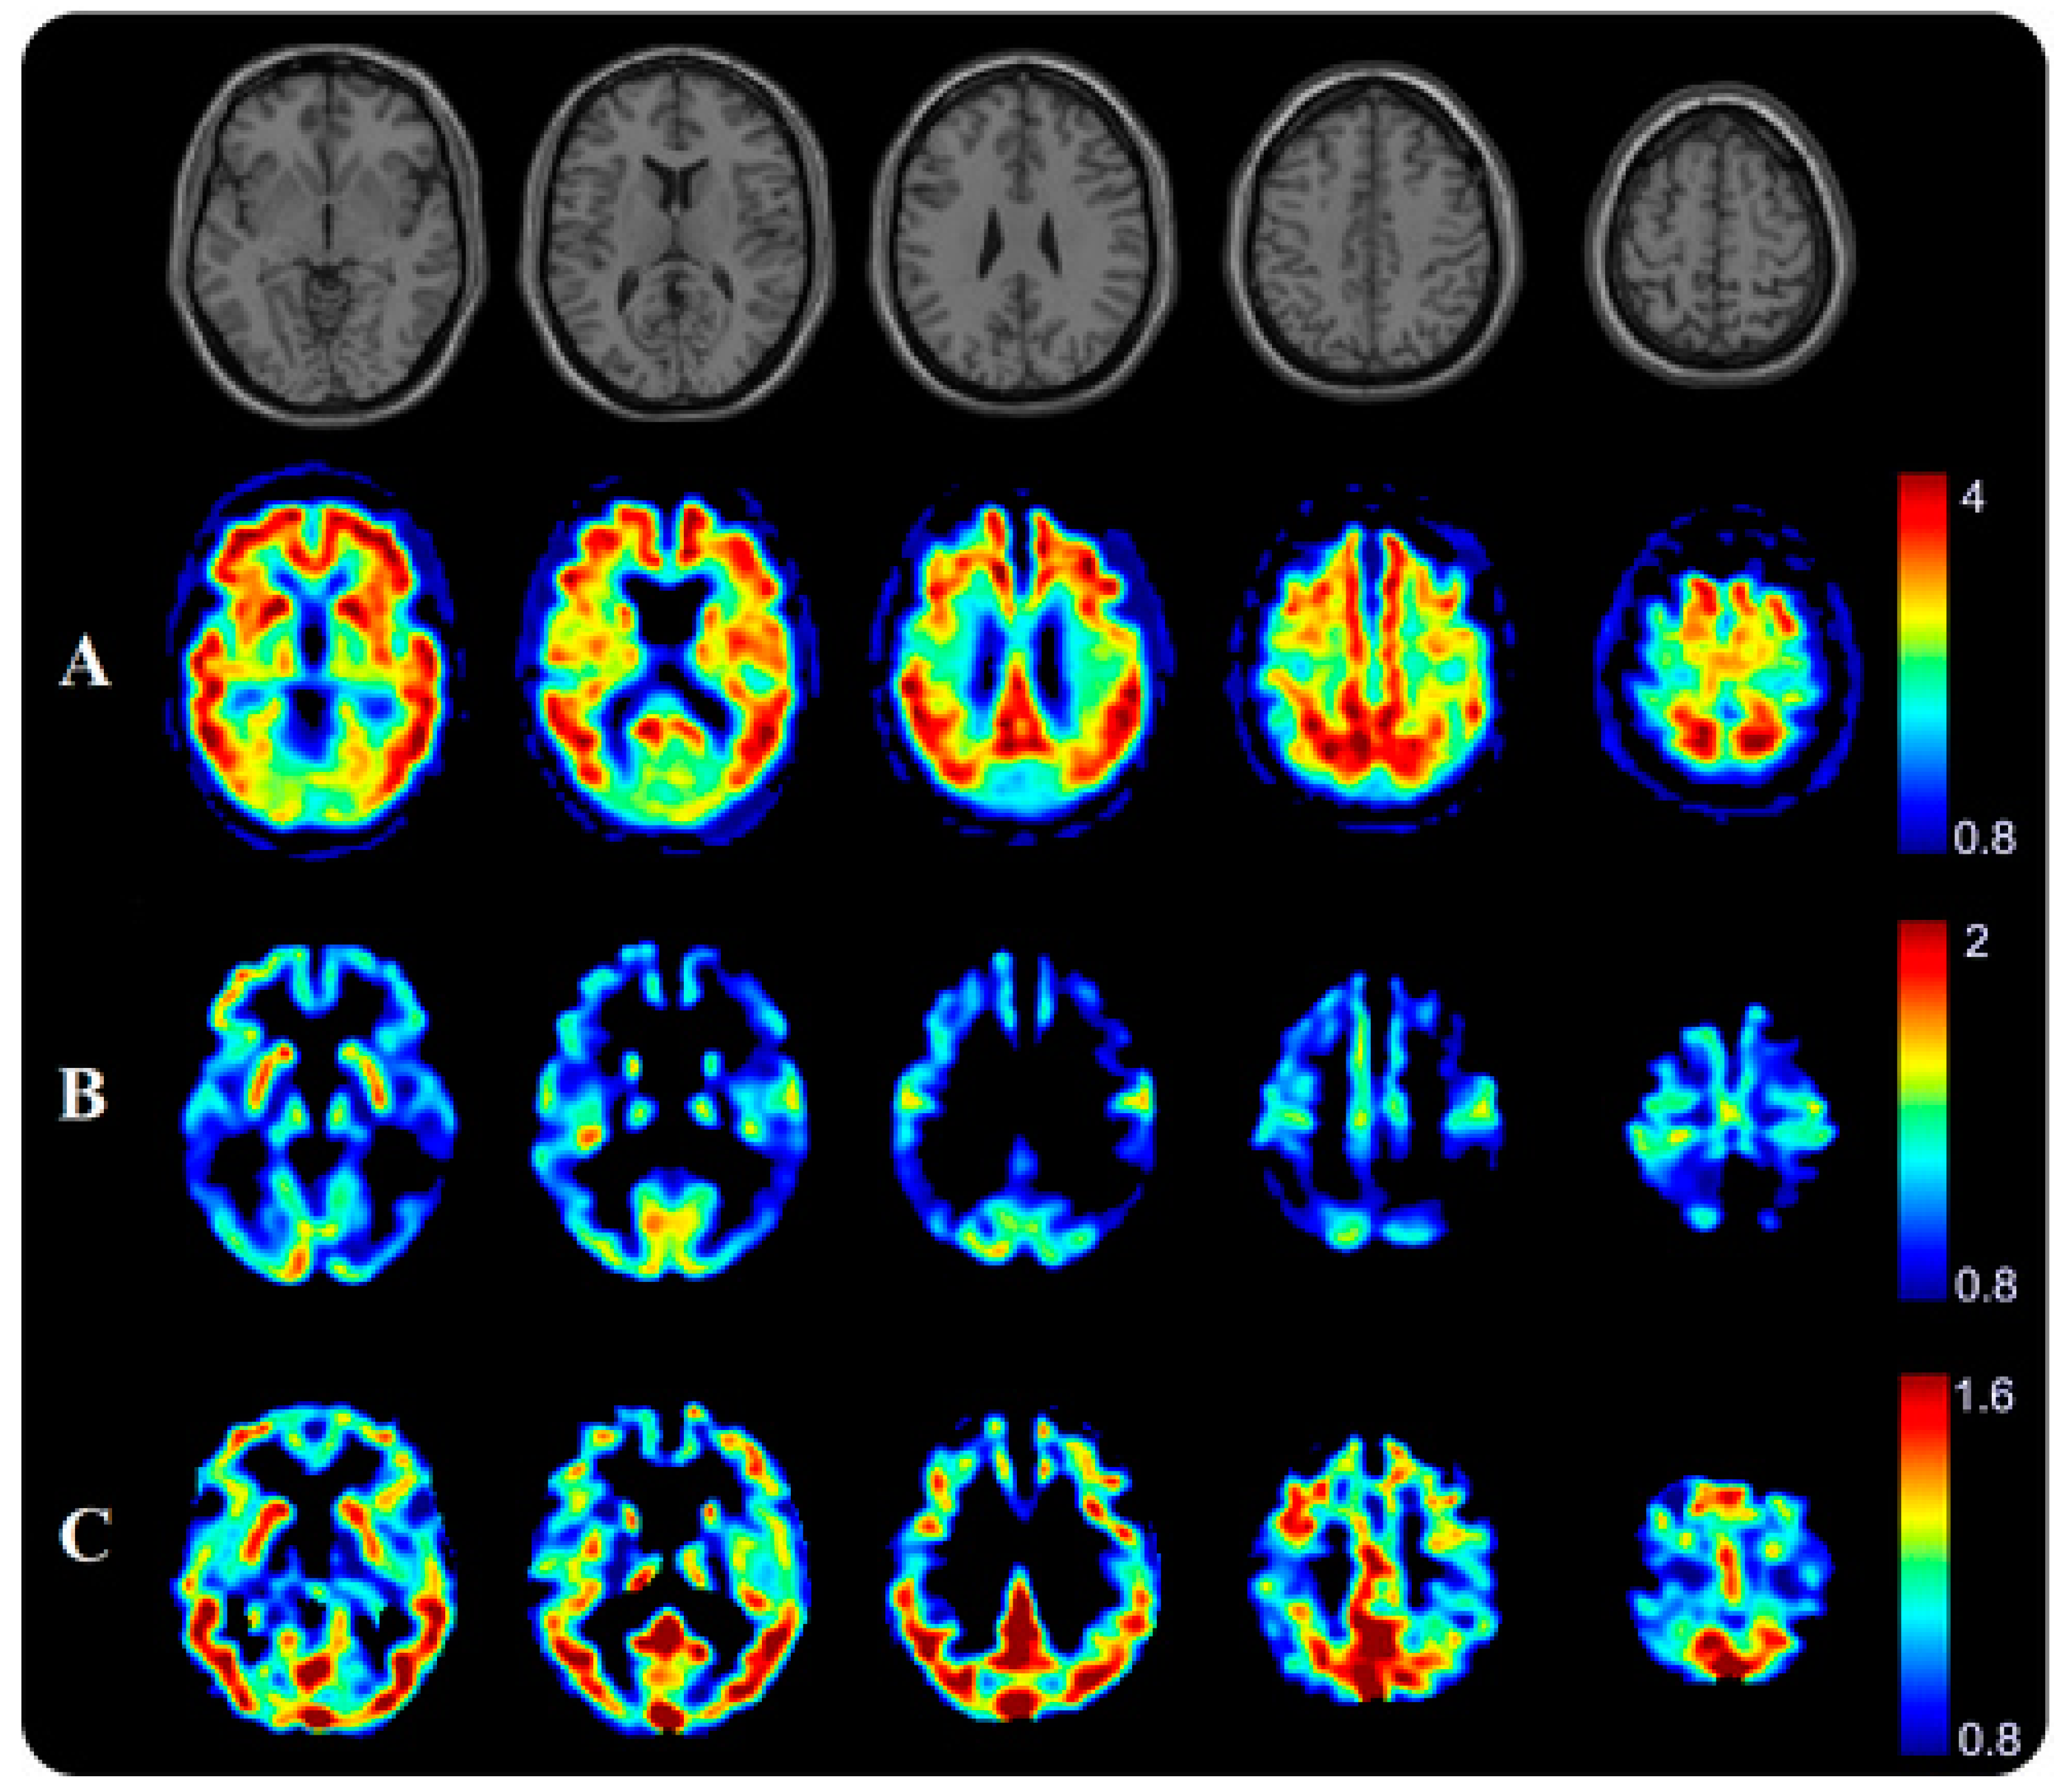

- Minoshima, S.; Cross, D.; Thientunyakit, T.; Foster, N.L.; Drzezga, A. 18F-FDG PET Imaging in Neurodegenerative Dementing Disorders: Insights into Subtype Classification, Emerging Disease Categories, and Mixed Dementia with Copathologies. J. Nucl. Med. 2022, 63, 2S–12S. [Google Scholar] [CrossRef]

- Della Rosa, P.A.; Cerami, C.; Gallivanone, F.; Prestia, A.; Caroli, A.; Castiglioni, I.; Gilardi, M.C.; Frisoni, G.; Friston, K.; Ashburner, J.; et al. A standardized [18F]-FDG-PET template for spatial normalization in statistical parametric mapping of dementia. Neuroinformatics 2014, 12, 575–593. [Google Scholar] [CrossRef] [PubMed]

- Perani, D.; Della Rosa, P.A.; Cerami, C.; Gallivanone, F.; Fallanca, F.; Vanoli, E.G.; Panzacchi, A.; Nobili, F.; Pappata, S.; Marcone, A.; et al. Validation of an optimized SPM procedure for FDG-PET in dementia diagnosis in a clinical setting. Neuroimage Clin. 2014, 6, 445–454. [Google Scholar] [CrossRef] [PubMed]